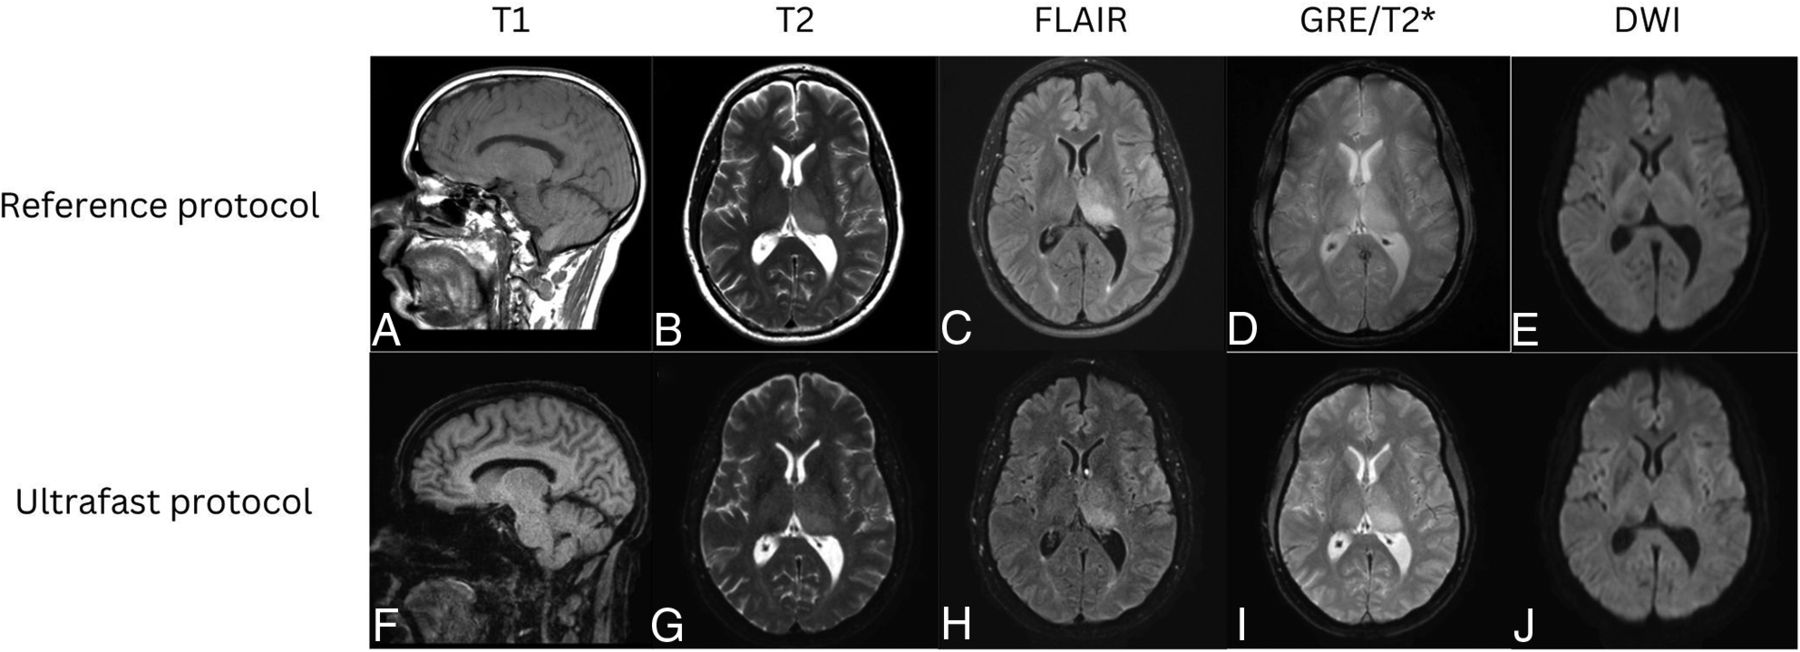

Representative images from 4 clinical cases are shown in Figures 3⇓⇓–6, demonstrating similar diagnostic quality between the ultrafast brain MR protocol images and the reference brain MR protocol images. Figure 3 shows a case of amyloid angiopathy with scattered foci of microhemorrhages. There is blurring of the findings on the reference GRE sequence due to motion artifact, and the foci of susceptibility signal are better appreciated on the ultrafast T2* images. Figure 4 shows a case of herpes simplex virus encephalitis with T2/FLAIR hyperintensity and restricted diffusion in the left greater than right mesial temporal lobes, visualized equally well on both the reference and the ultrafast brain MR protocols. Figure 5 shows a case of punctate subacute infarct in the left centrum semiovale on a background of chronic small vessel ischemic disease, visualized equally well on both the reference and the ultrafast brain MR protocols. Figure 6 shows a case of glioma involving the left thalamus with both the reference and the ultrafast brain MR protocol demonstrating ill-defined T2/FLAIR hyperintensity centered in the left thalamus.

Patient with punctate subacute infarct in the left corona radiata. Reference sagittal T1-weighted (A), axial T2-weighted (B), FLAIR (C), SWI (D), and DWI (E) show a punctate focus of restricted diffusion with associated FLAIR hyperintensity in the left centrum semiovale on a background of white matter T2/FLAIR hyperintensities that likely represent chronic small vessel ischemic disease. The same findings were seen on the ultrafast sagittal T1-weighted (F), axial T2-weighted (G), FLAIR (H), SWI (I), and DWI (J).